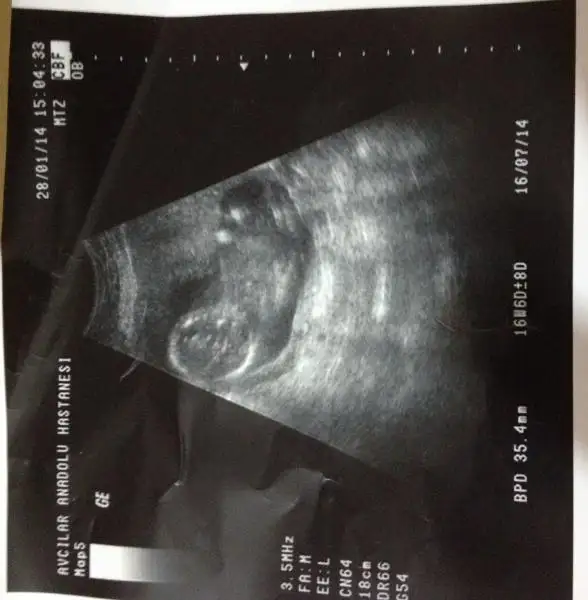

arkadaşlar bu ultrasyon resmide ablama ait ablam şuan 19 haftalık hamile ama dr lar hala net birşey diyemiyorlar belki siz bişiler dersiniz.

$bebeke4.webp $bebeke3.webp $bebeke1.webp $bebeke2.webp

kızlar ne olur cevaplayın=))